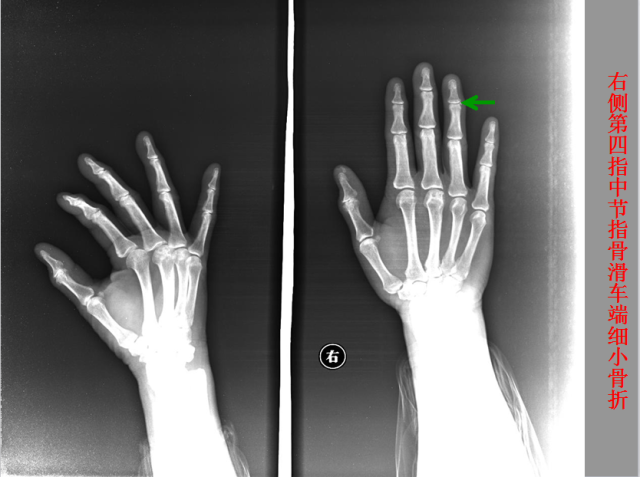

骨折篇

定义:骨折{Fracture}是指骨的完整性和连续性的折裂或粉碎。包括创伤性骨折、疲劳性骨折和病例理性骨折。 临床上以创伤性骨折*常见。